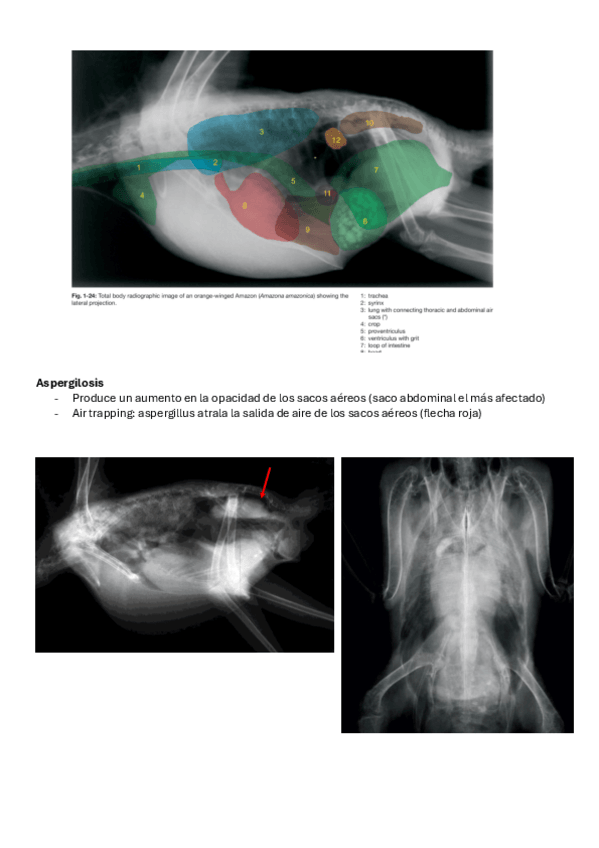

He publicado nuevos apuntes de 3º Diagnóstico Por Imagen: resumen-anatomia-exoticos.pdf

He publicado nuevos apuntes de 3º Diagnóstico Por Imagen: 29.-Anatomia-de-los-animales-exoticos.pdf